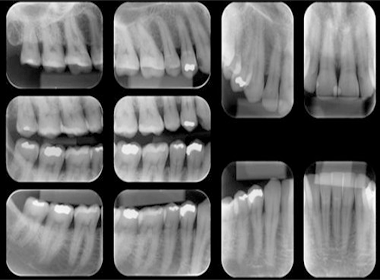

CRO/SP CL 8.832

R.T.: Marilen M. K. Kiyuna

CRO/SP 67.935